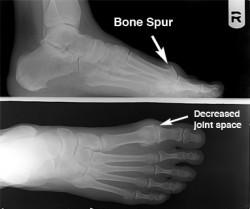

Arthritic first metatarsal joint with loss of motion.

This arthritic condition of the First Metatarsal Joint, results in loss of a very important motion necessary during gait. It, like most of the chronic pain conditions in the foot, is caused by the way we walk and stand. Certain foot types appear to be more prone to this particular condition, but gait is the causative part of the problem.